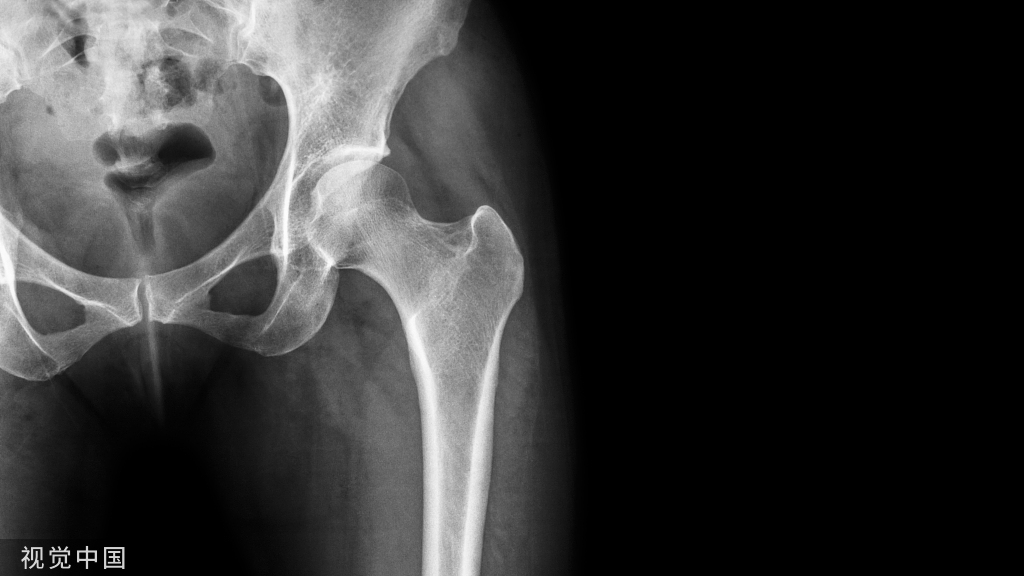

典型休门氏病患者X线片,终板不规则,多个中胸椎体轻度楔形改变,导致胸椎后凸增加 (PMID: 24509552)

典型休门氏病患者X线片:终板不规则+椎体楔型变 (PMID: 24468666)